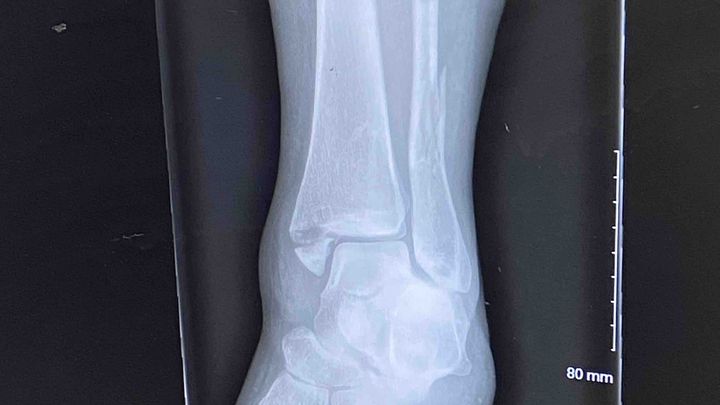

She had a rough landing which resulted in four fractures of her left ankle involving the fibula, tibia, and syndesmosis joint. Without an emergent ORIF surgery (open reduction and internal fixation) involving plates and screws to stabilize her ankle, the bones will heal incorrectly and she would be left with constant pain in the ankle/leg.